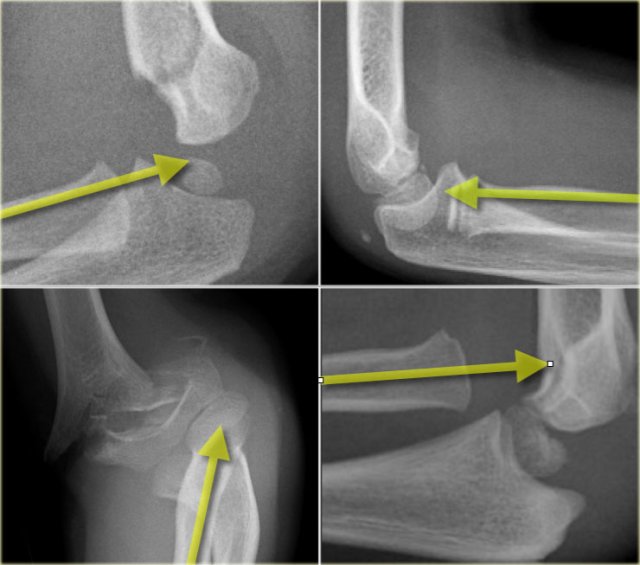

Capitellum fracture

While fractures of the lateral condyle occur in children between the age of 4 -10 years, isolated fractures of the capitellum are seen in children above the age of 12.

Capitellum fractures are uncommon.

The rotation of the fracture fragment gives a typical appearance on the X-rays (arrow).

Medial Epicondyle avulsion

The medial epicondyle is an apophysis since it does not contribute to the longitudinal growth of the humerus.

It is located on the dorsal side of the elbow.

On a lateral view especially if the arm is endorotated it can project so far posteriorly that one could suggest an avulsion (figure).

However avulsions are located more distally and anteriorly.

Since the medial epicondyle is an extra-articular structure a fracture or avulsion will not automatically produce a positive fat pad sign.